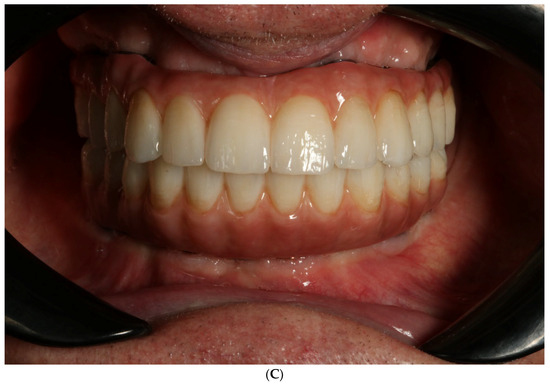

- Final restoration delivery with occlusal equilibration.